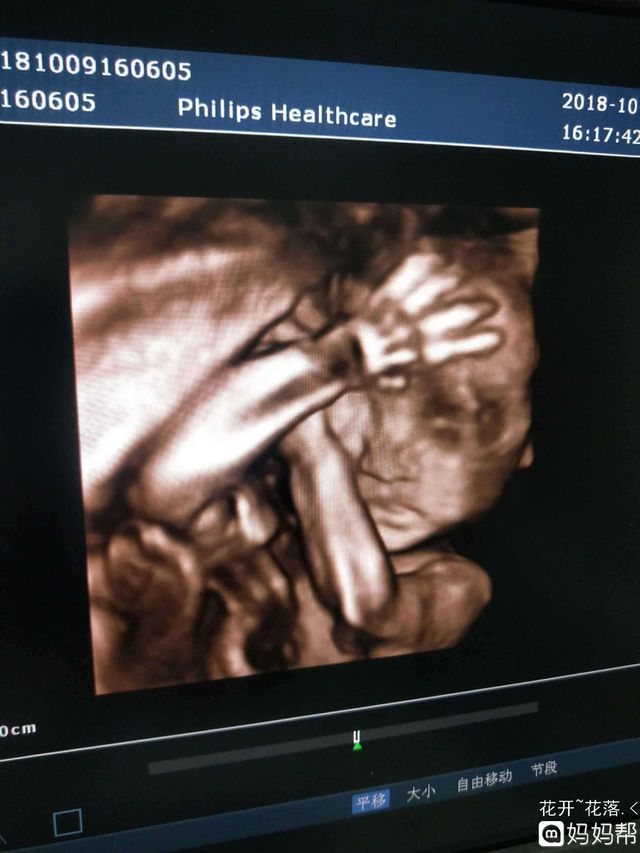

王主任:其他的都检查了,只有脸一直挡着

这样吧!你吃着巧克力,或者爬爬楼梯也许他会放下来

李洙赫小家伙真能折腾你妈妈

王主任:可以了这次可以看到了

李洙赫看到显示仪器上的图像

苏酒酒看着你在愣神,别光顾着看呀!快拿手机拍下来

李洙赫哦哦好